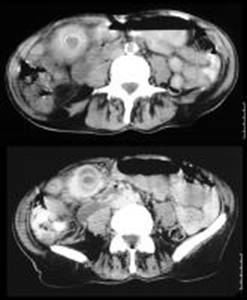

1.3.5 -Tac

Anche se poco usata, in

ragione degli alti costi e dei lunghi tempi,

Ispessimento della parete colecistica di più

di

Presenza di una aureola circostante la colecisti (segno indicativo di edema infiammatorio);

Fluido pericolecistico in assenza di ascite;

Slaminamento della mucosa colecistica;

Presenza di gas intramurale:

Tra i minori:

Dilatazione della colecisti;

Presenza di sludge all'interno della colecisti

La diagnosi alla Tac richiede la presenza di due criteri maggiori o uno maggiore e due minori.

Fig 5 Tac addome superiore . intensa reazione infiammatoria pericolecistica e perdita dell'interfaccia tra colecisti e tessuti circostanti